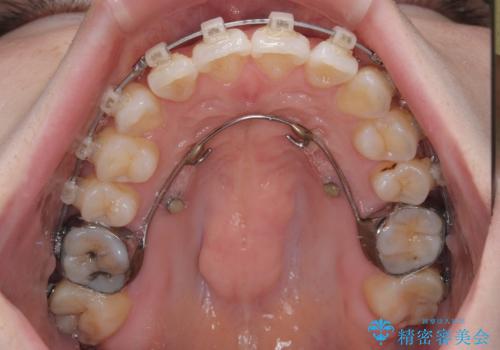

- クリアブラケット

補助装置を用いて上顎臼歯を後方移動させ、歯列を整えながら前歯部の接触を図ることとしました。

舌の突出癖改善のためのトレーニングを指導しながら、ワイヤー装置にて矯正治療を行うこととしました。